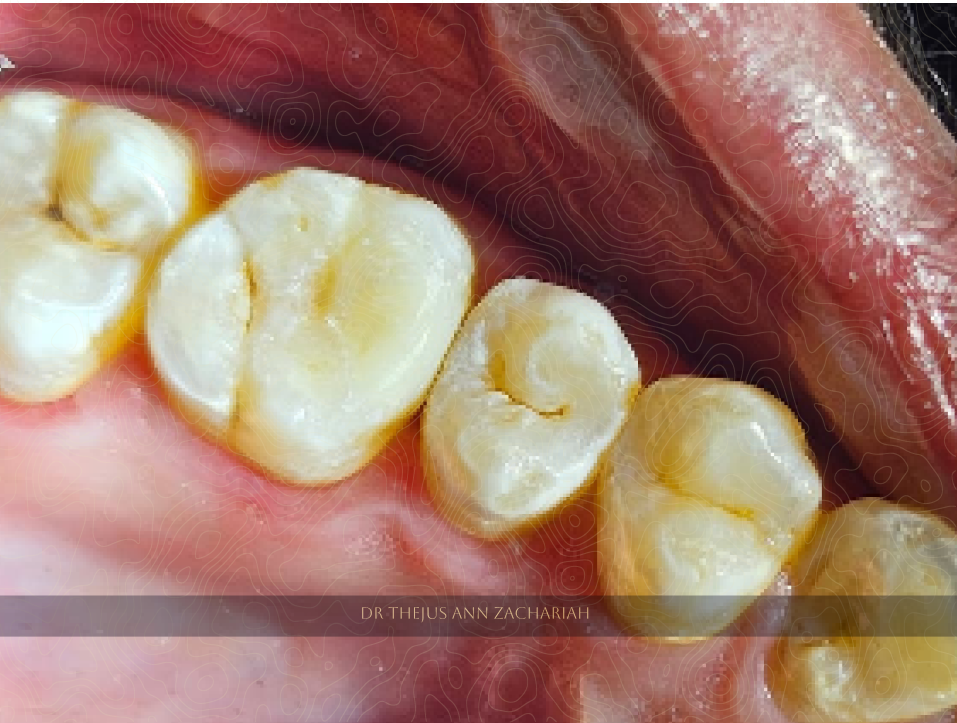

Post-Operative

alt text